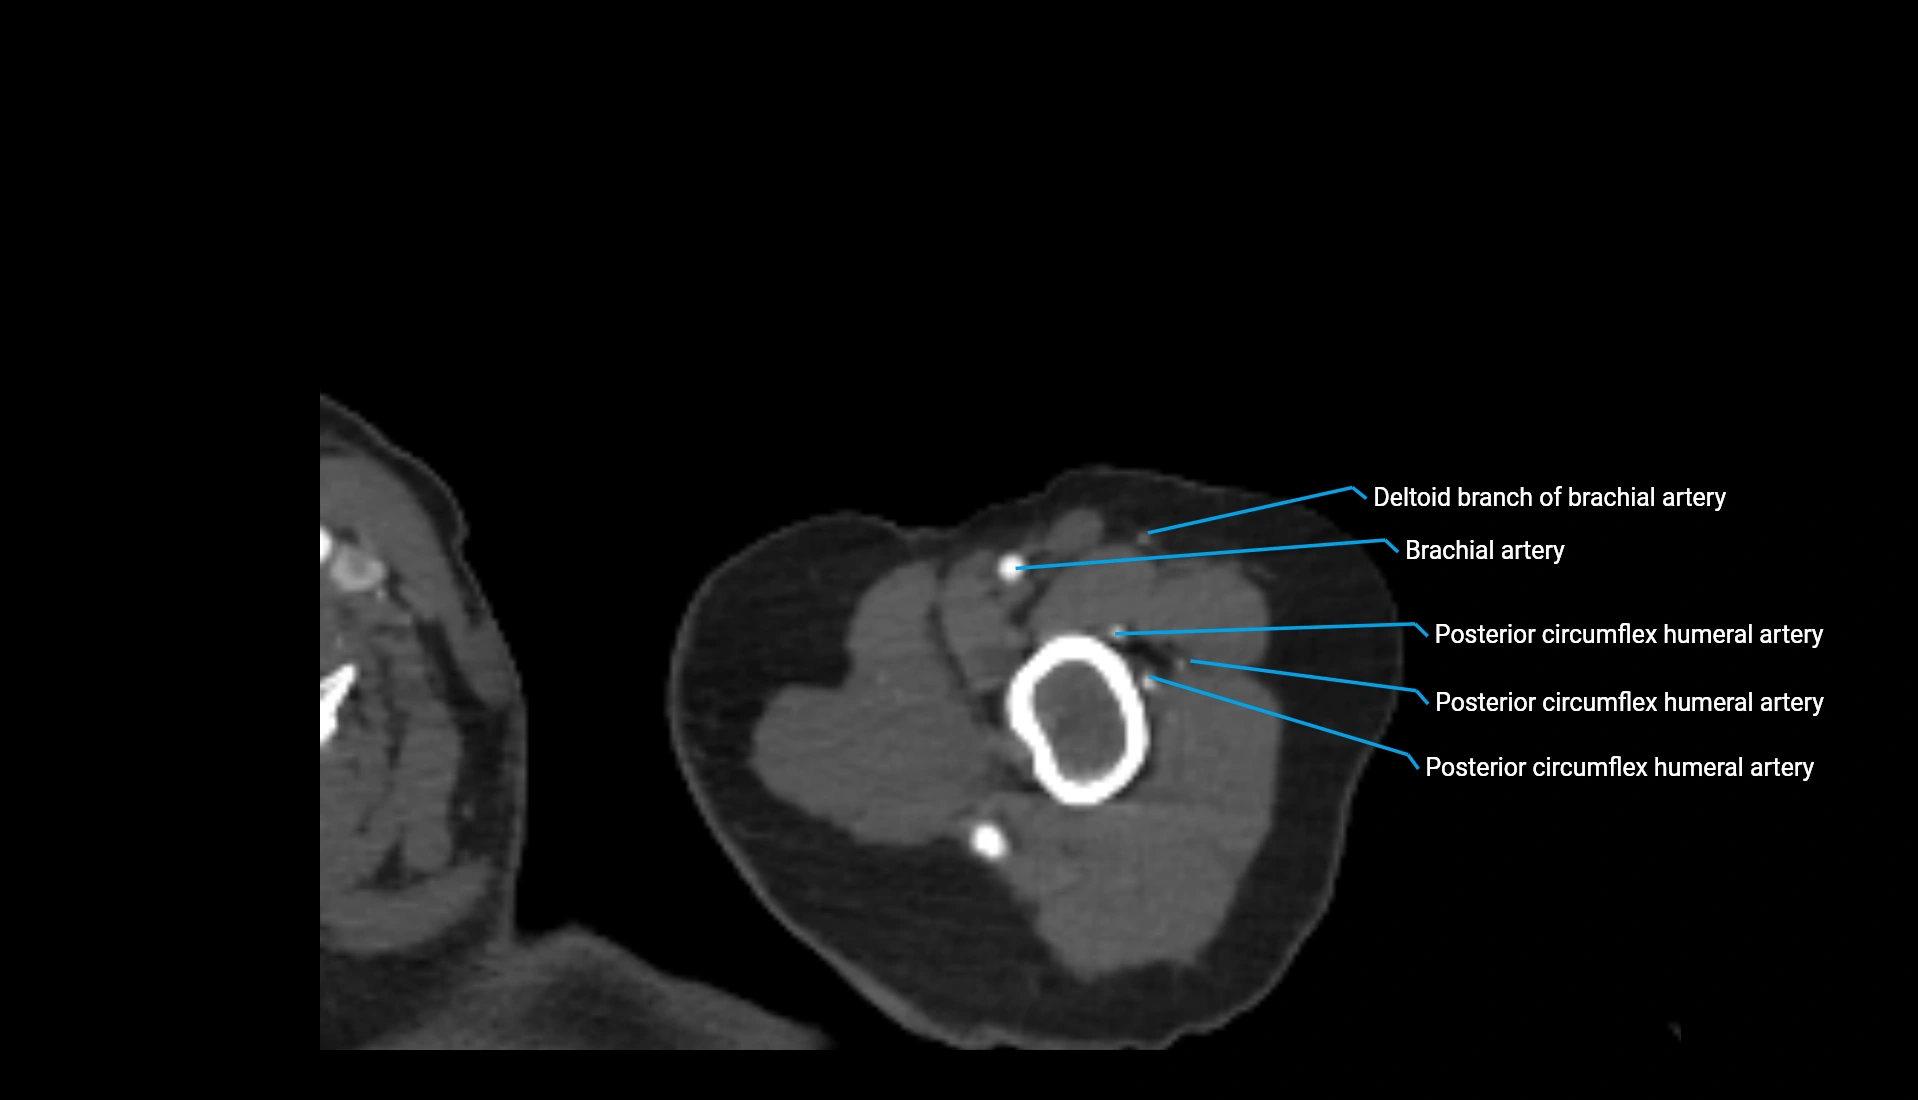

CT Appearance

Non-Contrast CT:

• Cortex: High-density, sharply defined

• Subchondral bone: Dense cancellous matrix

• Articular surface: Smooth concave contour articulating with the capitellum

• Excellent for evaluating bone integrity, alignment, and subtle fractures

Post-Contrast CT:

• Bone: No enhancement

• Joint capsule and synovium: Mild enhancement outlining the joint

• Improves contrast between soft tissues and bony margins

• Useful in detecting subtle joint abnormalities or postoperative changes